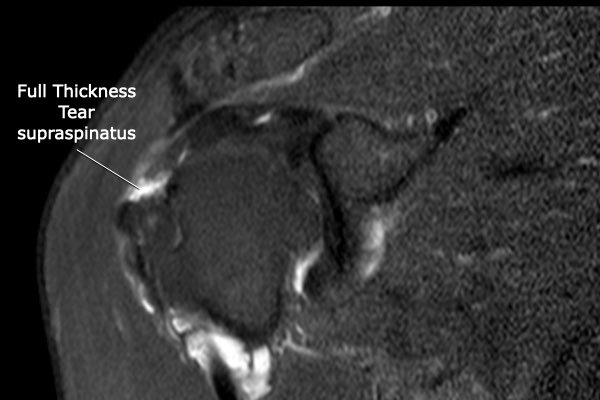

Rách toàn bộ chiều dày hoàn toàn

Nhấp vào hình ảnh để phóng to, sau đó cuộn qua các lát cắt.

Có hình ảnh rách toàn bộ chiều dày gân cơ trên gai kèm co rút và teo cơ.

Lưu ý các dải mỡ trong cơ tròn bé, cơ trên gai và cơ dưới gai.

Đo kích thước tổn thương rách toàn bộ chiều dày của chóp xoay theo hai chiều.